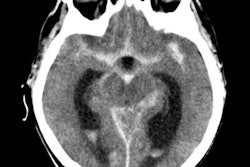

En una ecografía inicial del hombro no se observó ninguna anomalía que justificara los síntomas del paciente.

Se obtuvieron radiografías del hombro derecho del paciente. Haga clic en las imágenes siguientes para ampliarlas.